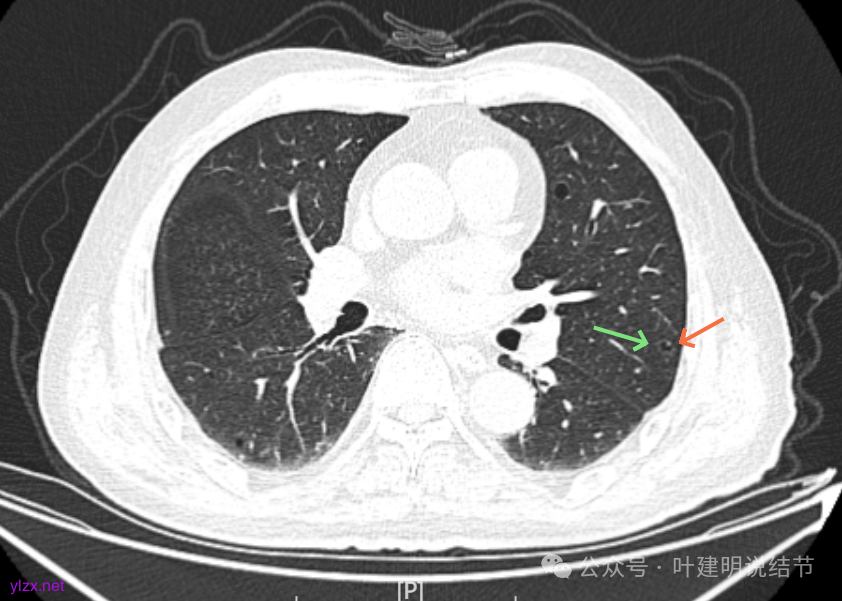

先来看2025年1月的影像:

病灶整体的囊壁稍不均,靠内侧有磨玻璃成分。

囊壁不厚但密度较高。

边缘区是淡磨,内壁少许突起。

右下叶也有囊腔灶。

两肺其他地方多处肺大泡。

左肺上叶红色这处是囊腔型病灶,囊壁略不均,似有微小血管进入囊壁,对比2023年4月整个囊腔来讲有扩大,需要考虑囊腔型肺癌的可能性大。右侧蓝色的并不是典型囊腔型肺癌的表现,再加上两肺绿色这些慢支肺气肿与肺大泡的影像,右侧的就更加不确切,至少近期不能够考虑右侧也要开刀的事情。其实左侧的主病灶相对于其他表现更典型的囊腔型肺癌来说,由于囊壁密度偏高,也不是百分百必定是肺癌。我的想法还是先等脑梗情况稳定,并且间隔4~6个月复查病灶再有进展在考虑单孔胸腔镜下局部切除就可以。淋巴结可以考虑采样,但一般不至于阳性。破是不会切破的。消融不建议,囊腔灶更难通过穿刺获得病理依据,况且东西在边上,能局部楔切,当然首选手术。意见供参考!

左侧这个病灶总体上看仍是囊腔型肺癌可能性大些,但因为其两肺存在多发肺大泡的基础,而且囊壁除了结节状高密度的以外,其他的部分虽欠均匀,但差别并不太大。所以100%恶性还是难以认定的。假如没有脑梗情况,位置在边上,早点切了明确并去除病灶当然是可行的。但在反复脑梗发作的情况下,本身要神经内科情况稳定再手术较为安全,加上无法确切认定必恶性,再适当的随访也不至于影响预后。所以仍是利弊权衡与如何平衡的事情。对于这种囊腔灶,或囊肿为表现的肺癌,其实穿刺不容易阳性,针越过组织的距离并不长,其内又是空的或是液体性质的。从临床经验来看,囊腔型肺癌若囊壁是实性的,确实低分化类型的更常见些,相对风险较高些。但若是囊壁磨玻璃成分的,则也仍是贴壁为主型多见。而且从大小来讲,个人总觉得囊腔部分不能算大小,肿瘤的有形成分应该是减去空腔部分的,所以不能认定CT上测量的包括囊腔部分的来算肿瘤大小的T值。